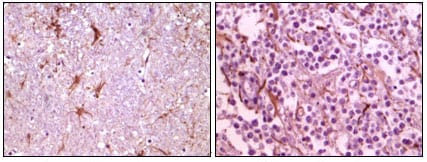

分类: 科研抗体货号: 20087别名: CIB; KIP; KIP1; SIP2-28应用: WB,IHC反应种属: Human

分类: 科研抗体货号: 20086别名: MGC10442应用: WB,IHC反应种属: Human